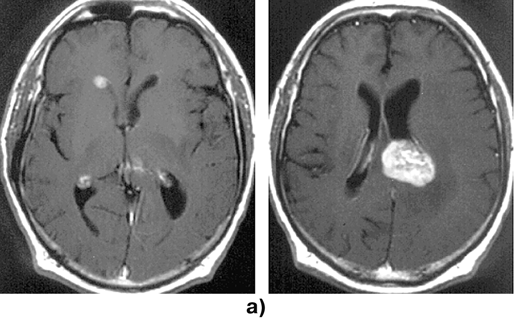

На МРТ или КТ (рис. 1) первичные лимфомы головного мозга в основном выглядят как объемные сóлидные образования гомогенно повышенной плотности, реже выявляются гипо— или изоденсные очаги. Больше 90% лимфом накапливают контраст, при этом гомогенное накопление контраста наиболее типично. Реже контрастное усиление происходит по периферии новообразования в виде кольца или не происходит вообще. В 10–30% случаев выявляется множественное поражение. Опухоли чаще располагаются супратенториально (лобные доли, подкорковые узлы, мозолистое тело, перивентрикулярно); субтенториальное распространение отмечается приблизительно в 25%, в основном в мозжечке; ствол мозга и спинной мозг поражаются редко. Первичные лимфомы ЦНС обычно локализуются в паренхиме мозга в отличие от системных лимфом («вторичное» поражение), при которых имеется лептоменингиальное распространение.

Рисунок 1. Первичные лимфомы ЦНС:

а — множественная первичная лимфома головного мозга (МРТ, Т1-взвешенные изображения с контрастным усилением, аксиальная проекция); б — лимфома медиальных отделов лобных долей, с обеих сторон распространяющаяся на колено мозолистого тела (до и через 1 год после стереотаксической биопсии и комбинированного лечения) (КТ с контрастным усилением, аксиальная проекция)

Предположение о первичной лимфоме ЦНС должно возникать всякий раз, когда на КТ обнаруживается гомогенное объемное образование повышенной плотности, особенно расположенное паравентрикулярно или вблизи от мозолистого тела и других срединных структур. Обнаружение двусторонних симметричных субэпендимарных очагов повышенной плотности подтверждает диагноз первичной лимфомы ЦНС. Перитуморозный отек, как правило, выражен меньше, чем при злокачественных глиомах и метастазах. Применение стероидов обычно приводит к существенному уменьшению и даже к исчезновению лимфом, по данным КТ или МРТ.